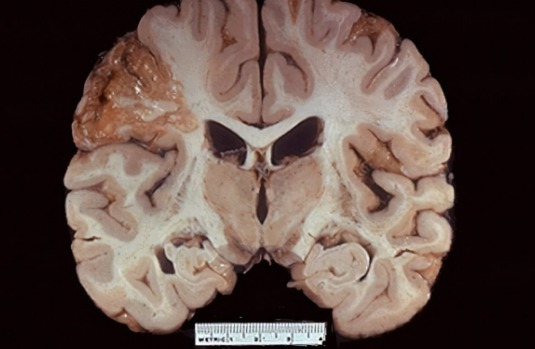

Aquí se ve como en la parte de la derecha sigue habiendo células con núcleos y se van haciendo células con alteraciones- perdida de núcleos o mejor dicho eosinófilo (rosita) amorfo sin núcleos=

Necrosis coagulativa